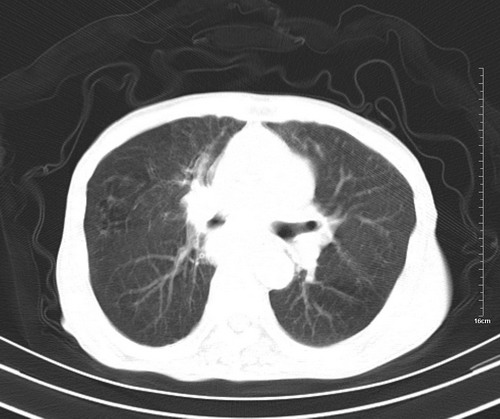

病人,女,79岁,主要因腹疼二月入院,彩超,肝,胆,脾,未见异常,胸透上消化道造影未见异常,化验白细胞增高,内科医生让做胸部ct检查,因为熟人多做了腹部(外科会诊考虑胆囊炎).现ct片如下请假各位战友.

肺癌,纵隔淋巴结转移,肝左叶病变考虑为转移病灶。

后中纵隔团块影,伴气管、食道受压移位,首先考虑转移瘤,肝s5段低密度灶。建议增强检查,另外其结肠是否有问题请提供,右肺部分肺叶局限含气增多,考虑局限肺气肿。

建议强化检查,考虑纵隔型肺癌,小细胞可能性大。